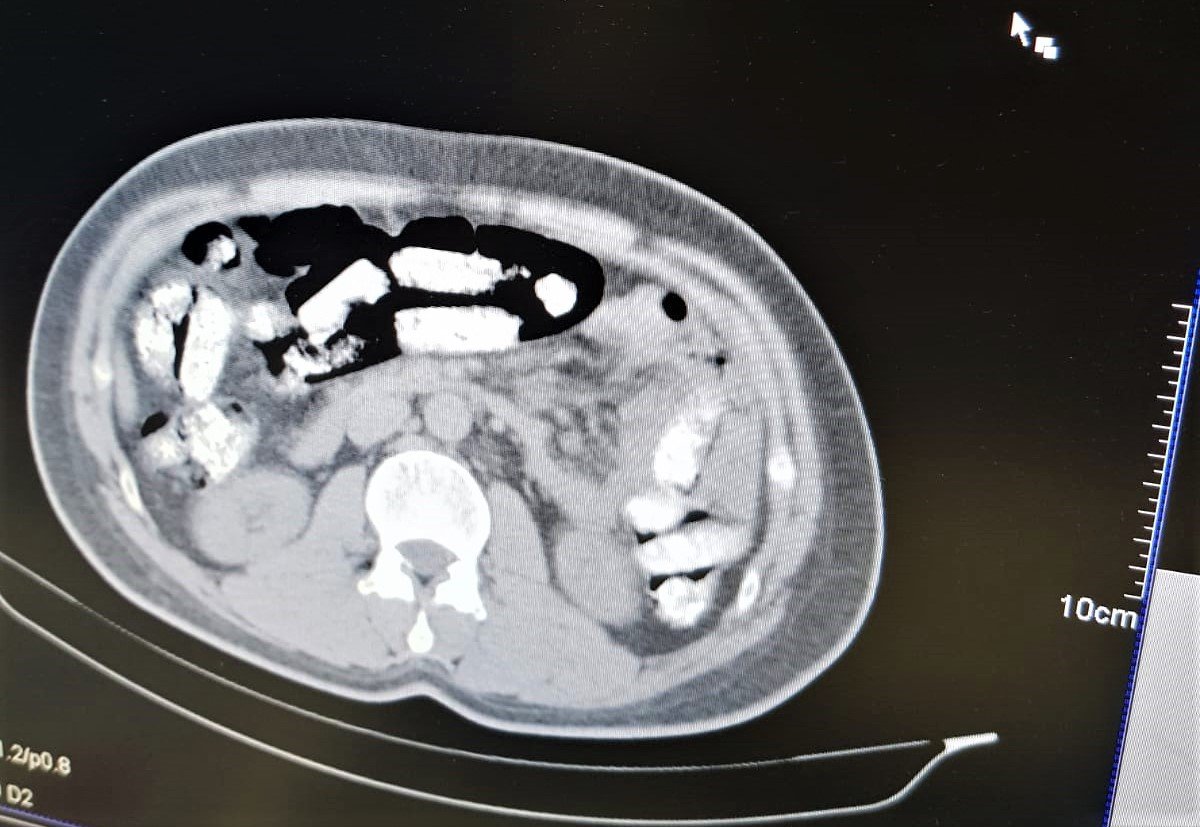

Erzincan İl Emniyet Müdürlüğü Narkotik Suçlarla Mücadele Şube Müdürlüğü ekiplerince uyuşturucu madde kuryeliği yapan şahıslara yönelik İran otobüsleri üzerinde yapılan uygulamada; İran otobüsünde yolculuk yapan Abdulmennan S. isimli İran uyruklu kişinin yutma yöntemiyle uyuşturucu taşıdığı değerlendirilmesi üzerine, Erzincan Mengücek Gazi Eğitim ve Araştırma Hastanesinde zanlının bedeninden 106 fişek halinde toplamda 1 kilo 198 gram Afyon Sakızı ele geçirildi. Abdulmennan S. hakkında TCK 188 suçundan yapılan tahkikat sonrası sevk edildiği mahkemece tutuklanarak cezaevine teslim gönderildi.